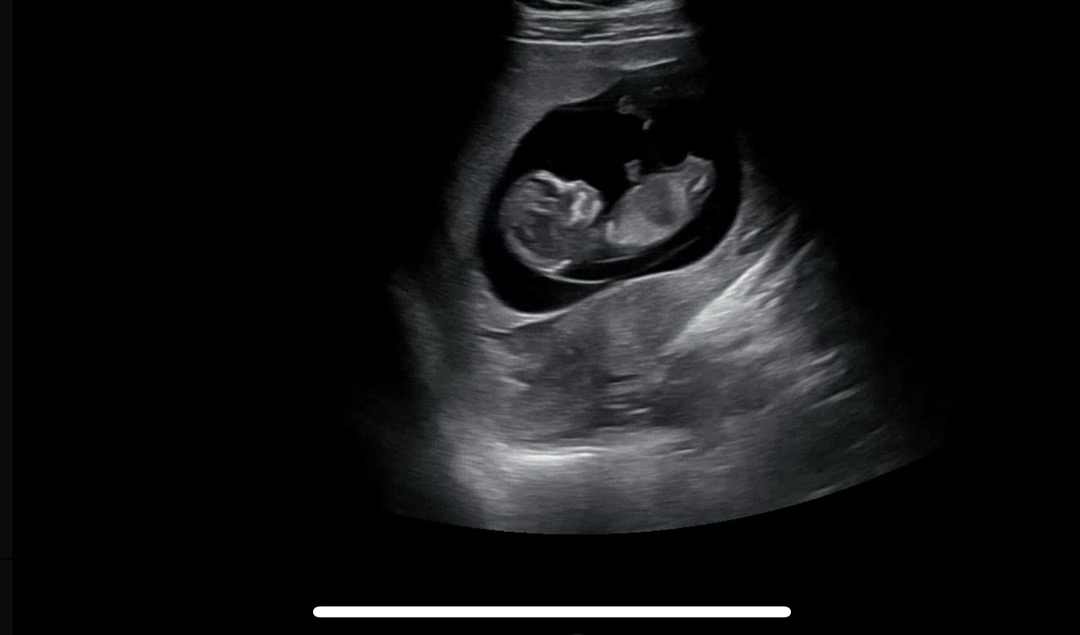

각도법 보시는 분🥹

11주차 2일에 찍은 초음파인데 딸같나요 아들같나요..🤨